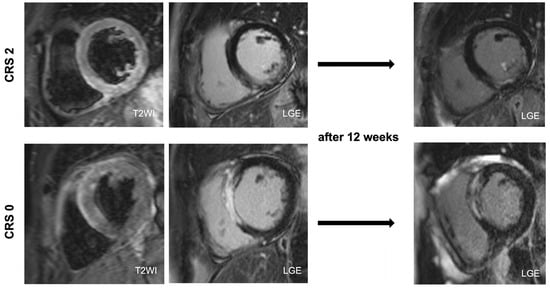

2.3. Cardiovascular Magnetic Resonance

| Infarct size at baseline, % | 23 (±11) | 14 (±5) | 0.004 |

| Final infarct size, % | 20 (±12) | 7 (±4) | <0.001 |

| I/R edema at baseline, % | 44 (±12) | 36 (±11) | 0.098 |

| Myocardial salvage index, % | 57 (±19) | 78 (14) | 0.006 |